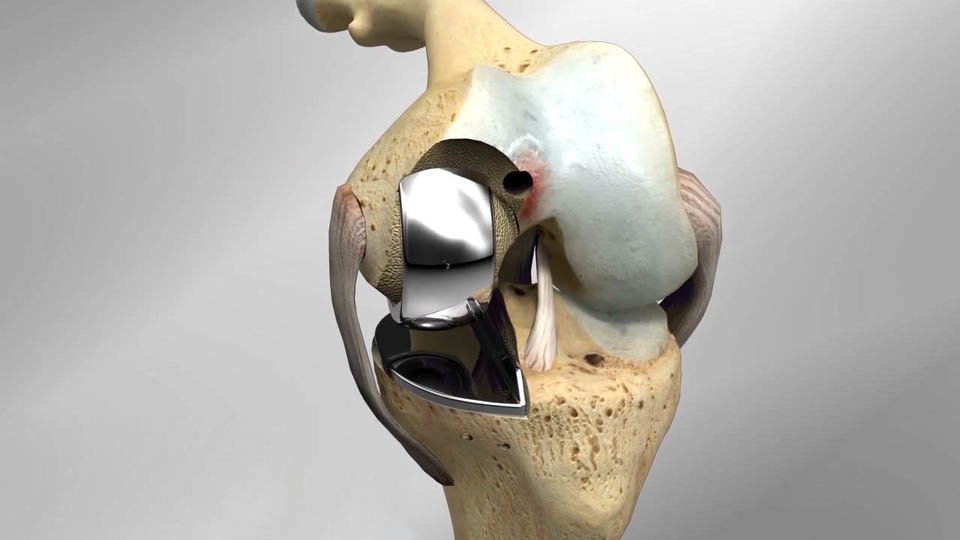

Partial Knee Replacement, also known as Microplasty, is a minimally invasive surgical procedure performed when arthritis affects only one part of the knee. Dr. Nevil K. Gajera offers this precision surgery to restore mobility, reduce pain, and preserve the natural movement of the knee.

Unlike total knee replacement, Microplasty retains healthy parts of the knee, ensuring a more natural feel and function. It involves a smaller incision, less tissue disruption, and quicker rehabilitation, allowing patients to return to their daily activities faster.